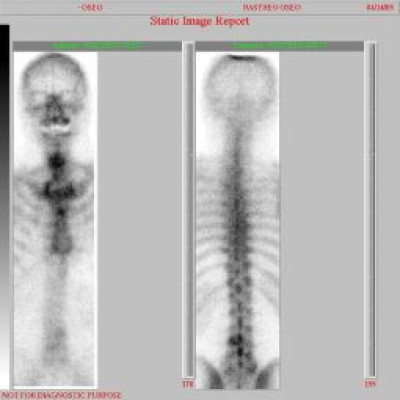

Metástasis óseas por cáncer de prostata

Envíado por Instituto Nacional de Cardiología y Cirugía Cardiovascular